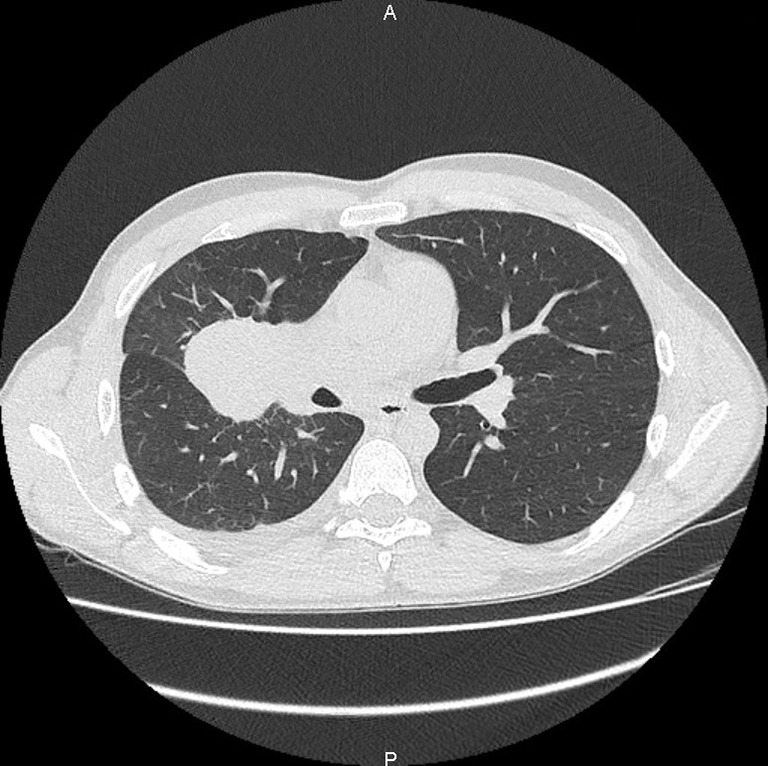

背景:IV期非小细胞肺癌不是一个可治愈的阶段。然而,一种局部治疗原发肿瘤的新方法可能会提高无进展生存期。放疗或手术的选择,以及这些治疗的最佳时机仍有待确定。我们在这里报告第一例,据我们所知,一个多转移患者在新辅助阿勒替尼治疗后接受巩固手术,导致完全的病理反应。病例描述:该患者是典型的致癌改变人群,如间变性淋巴瘤激酶(ALK)重排,年轻,不吸烟;然而,他是男性。支气管内窥镜检查证实支气管肺腺癌,免疫组化显示ALK强表达。我们启动了alectinib作为转移性疾病的一线治疗;然而,由于诱导的低转移性疾病,在多学科委员会上讨论了原发肿瘤的局部治疗。行肺叶切除术,组织学检查证实完全病理反应。由于缺乏可用数据,佐剂alectinib持续时间未确定。结论:该病例提示,局部治疗,即使是IV期患者,在对全身治疗有最佳反应的时候进行,可能会改善无进展生存期,甚至可能是治愈的一瞥。

Case description: The patient was, as is typically observed in populations with oncogenic alterations such as anaplastic lymphoma kinase (ALK) rearrangements, a young and non-smoker; however, he was male. Bronchial endoscopy confirmed the diagnosis of bronchopulmonary adenocarcinoma with strong ALK expression demonstrated by immunohistochemistry. We initiated alectinib as first-line treatment for metastatic disease; however, due to the induced oligo-metastatic disease, a local treatment of the primary tumor was discussed during multidisciplinary board. Lobectomy was performed and histological examination confirmed the complete pathological response. Adjuvant alectinib was continued for unspecified duration due to the lack of available data.